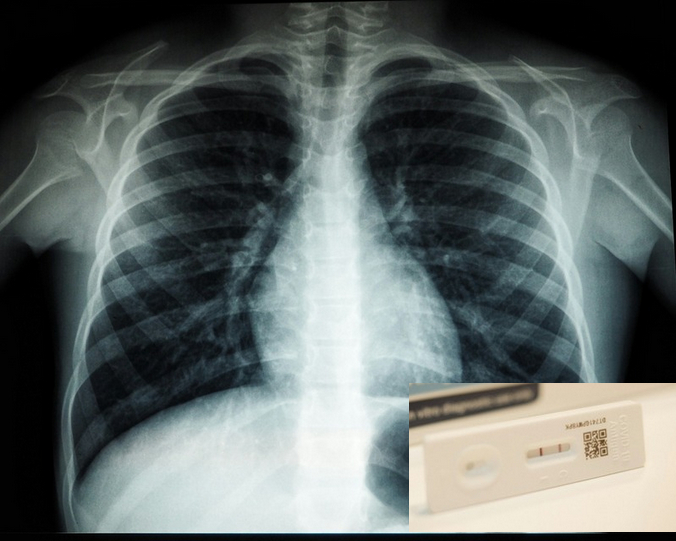

Neue Erkenntnisse aus den USA deuten nun darauf hin, dass schwere Atemwegserkrankungen wie COVID-19 oder eine heftige Influenza das Risiko für Lungenkrebs signifikant erhöhen könnten. Forscher warnen davor, dass die durch Viren verursachten Schäden den Boden für bösartige Tumore bereiten.

Ein Team der University of Virginia unter der Leitung von Jie Sun hat untersucht, wie virale Infektionen das Lungengewebe langfristig verändern. Die Ergebnisse sind beunruhigend: Eine schwere Erkrankung versetzt das Organ in einen dauerhaften Entzündungszustand. Laut Jie Sun werden dabei Immunzellen derart umprogrammiert, dass sie ihre Schutzfunktion verlieren und stattdessen das Krebswachstum begünstigen.

Die Wissenschaftler stützten ihre Thesen nicht nur auf Tierversuche, sondern auch auf die Auswertung umfangreicher Patientendaten. Dabei zeigte sich ein klarer Trend: Personen, die aufgrund von Corona im Krankenhaus behandelt werden mussten, erkrankten später häufiger an Lungenkrebs. Dieser Zusammenhang blieb auch dann bestehen, wenn Faktoren wie die individuelle Rauchervorgeschichte oder Vorerkrankungen herausgerechnet wurden.